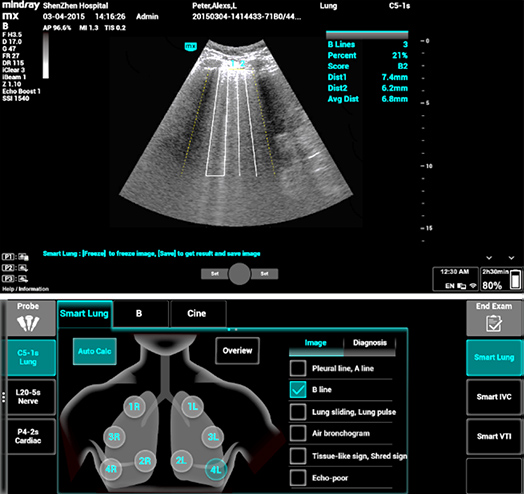

1Smart B-line

Cuenta autom√°ticamente la cantidad de l√≠neas B y el porcentaje del √°rea de las l√≠neas B en funci√≥n de los protocolos y asigna un puntaje al funcionamiento del pulm√≥n en cuatro patrones seg√Їn la aireaci√≥n pulmonar. La descripci√≥n general de la imagen y el mapa a color del puntaje pueden ayudar en la evaluaci√≥n de la funci√≥n pulmonar.

1